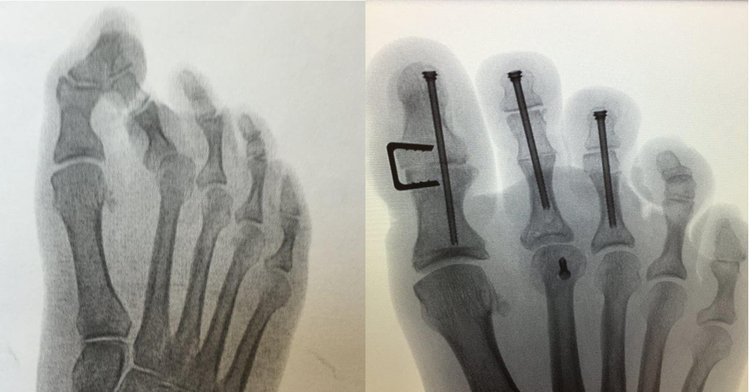

The ALPHALOK METFX Plating System provides a comprehensive range of anatomicly contoured fracture and fusion plates specifically designed for the fore and midfoot.

ALPHALOK features low-profile 1.3mm Type II anodized plates that accept 1.5mm, 2.0mm, and 2.5mm polyaxial locking screws that can be angled ±15° for a total range of 30°.